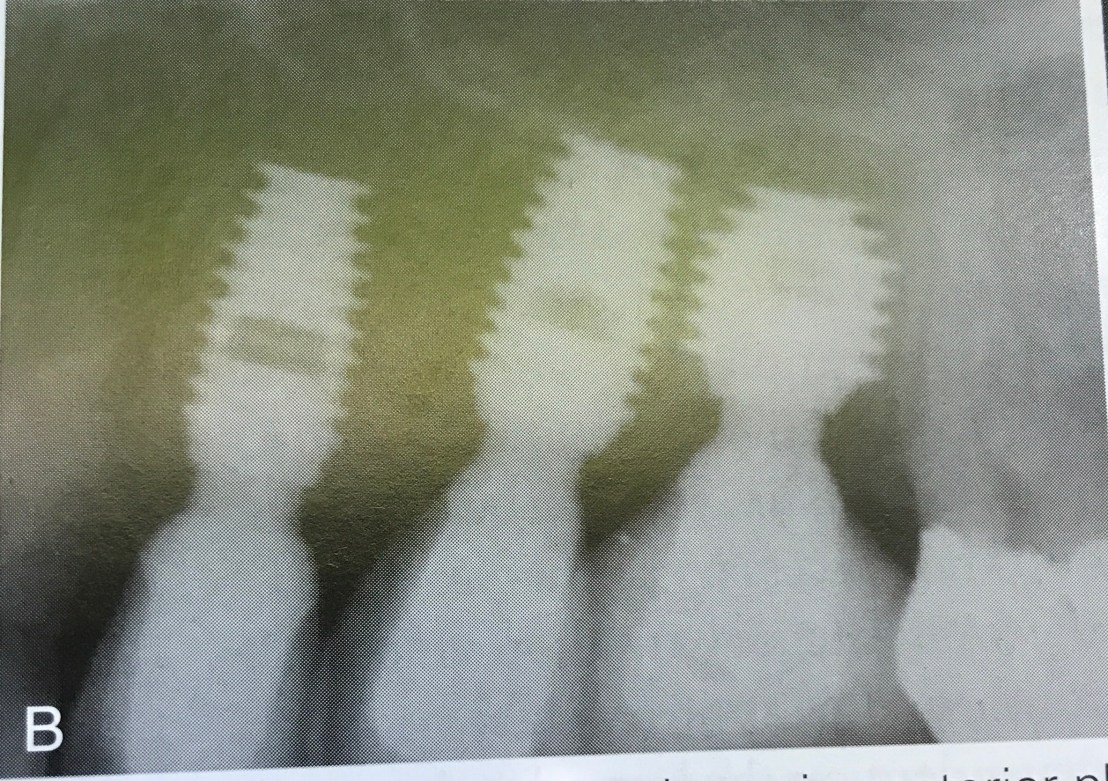

แสดงการ Gain Primary stability โดยการใช้ Osteotome (รูป B คือหลังใช้ Osteotome)

แสดงความผิดพลาดในการวางตำแหน่ง จะเห็นได้ว่า แม้จะมี socket ถอนฟันเป็นตัว guide แต่ตำแหน่งที่ฝังยังออกไป Distal มาก

ดังนั้นการใช้ข้อมูลจาก X-ray + Surgical stent จึงยังเป็นสิ่งจำเป็นอยู่ แม้ในเคส Immediate ก็ตาม